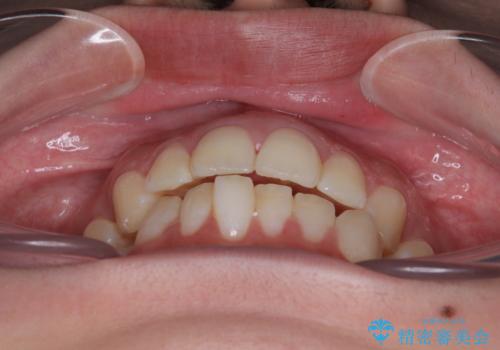

診察してみると、下の前歯が並ぶためのスペースが足りないことが、歯並びがデコボコしている原因でした。

そこで今回は、以下の2つの方法を組み合わせて治療を行いました:

下の前歯の歯と歯の間をわずかに削ってスペースを作る(IPR)

奥歯を後ろに動かして、前歯が並ぶためのスペースを確保する